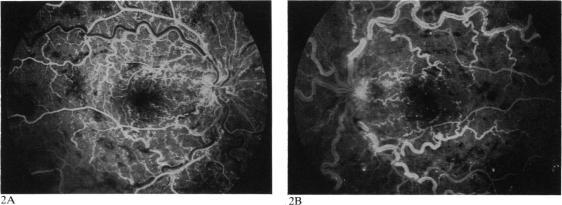

A patient with Waldenström's macroglobulinaemia presented with visual reduction in both eyes. The funduscopic and angiographic demonstrations of venous engorgement ('string of sausages'), retinal haemorrhages at all levels, retinal and disc oedema, and serous detachment of the maculas were consistent with this diagnosis. The cryoprecipitation of the immunoglobulin at a temperature slightly below body temperature precluded routine blood studies and plasmapheresis. Plasmapheresis was ultimately performed without difficulty with the patient and equipment at 88 degrees F (31 degrees C). Despite marked improvement in the funduscopic and angiographic appearance of the retina, perifoveal capillary nonperfusion and serous elevation of the macula persisted. Even when the maculas flattened in both eyes, no visual recovery occurred. Early diagnosis, even on a clinical basis when laboratory studies cannot be performed, and early plasmapheresis to reduce serum viscosity are warranted to prevent intravascular occlusion in the perifoveal capillary bed, deposition of immunoglobulin in the retina, and transudation in the subretinal space.

一名华氏巨球蛋白血症患者出现双眼视力下降。眼底镜检查和血管造影显示静脉充血(“香肠串”样)、各层视网膜出血、视网膜及视盘水肿以及黄斑浆液性脱离,这些均与该诊断相符。免疫球蛋白在略低于体温的温度下发生冷沉淀,这使得常规血液检查和血浆置换无法进行。最终,在患者体温为88华氏度(31摄氏度)时,使用该患者和设备顺利进行了血浆置换。尽管视网膜的眼底镜检查和血管造影表现有明显改善,但黄斑周围毛细血管无灌注及黄斑浆液性隆起仍持续存在。即使双眼黄斑变平,视力也未恢复。即使在无法进行实验室检查的临床基础上,早期诊断以及早期进行血浆置换以降低血清粘度对于预防黄斑周围毛细血管床的血管内阻塞、视网膜免疫球蛋白沉积以及视网膜下间隙的渗出都是必要的。